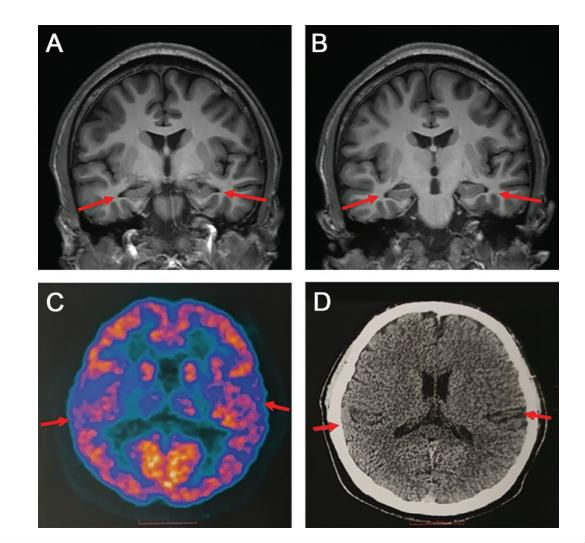

近日消息,據北青網報道,一篇由首都醫科大學宣武醫院賈建平團隊撰寫的論文,發布在了國際知名阿爾茲海默病研究刊物上,文中介紹,一名來醫院就診的19歲男孩被臨床診斷為阿爾茲海默癥患者,而他也是目前已知的最年輕的患者。

由于年紀實在太小,以至于讓醫生都懷疑檢查結果,最終通過多種檢測,包括業界最為權威的手段,最終確認該男子的確患上了這種病。

據了解,該男子因為記憶衰退而拉倒醫院求醫,他的病情很嚴重,無法記起頭一天發生的事,又或者忘記自己的物品放在哪里,甚至會忘記只有沒有吃東西,由于病情嚴重,不得已而退學。